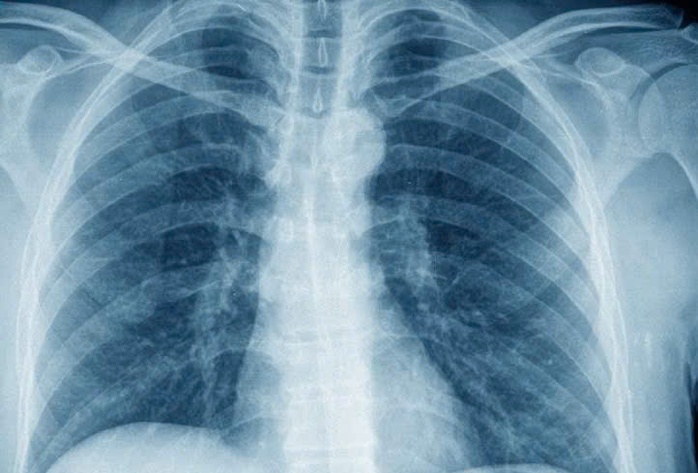

Trước phản ánh về việc chụp X-quang dưới 6 phút không được quỹ BHYT thanh toán, Bộ Y tế cho biết sẽ sớm tháo gỡ, bảo đảm quyền lợi người bệnh (Ảnh: Ngọc Dung)

Thông tin tại hội nghị triển khai công tác khám, chữa bệnh tổ chức ngày 2-2 tại TPHCM, lãnh đạo Cục Quản lý khám, chữa bệnh (Bộ Y tế) cho biết Bộ Y tế sẽ sớm tháo gỡ vướng mắc liên quan việc thanh toán BHYT đối với các ca chụp X-quang thực hiện dưới 6 phút, bảo đảm quyền lợi người bệnh và chi phí thực tế của các cơ sở khám, chữa bệnh.

Theo phản ánh, quy định định mức thời gian chụp X-quang tối thiểu 6 phút gây khó khăn cho bệnh viện trong thanh toán BHYT, do nhiều ca bệnh đơn giản có thời gian thực hiện ngắn hơn.